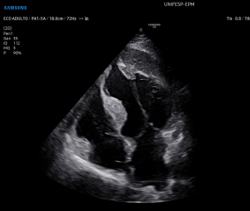

Septal hypertrophy